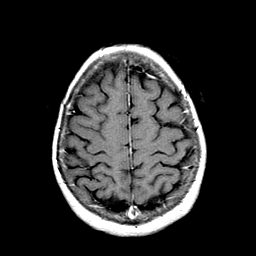

Metastatic Adenocarcinoma of the Colon: T1-weighted MR -- Slice #19

[Home][Help][Clinical] Slice 19